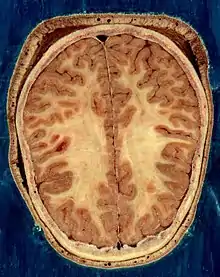

Horizontal section of the head of an adult female human, showing skin, skull, and brain with gray matter (brown in this image) and underlying white matter

The vertebrate nervous system can also be divided into areas called gray matter and white matter.[19] Gray matter (which is only gray in preserved tissue, and is better described as pink or light brown in living tissue) contains a high proportion of cell bodies of neurons. White matter is composed mainly of myelinated axons, and takes its color from the myelin. White matter includes all of the nerves, and much of the interior of the brain and spinal cord. Gray matter is found in clusters of neurons in the brain and spinal cord, and in cortical layers that line their surfaces. There is an anatomical convention that a cluster of neurons in the brain or spinal cord is called a nucleus, whereas a cluster of neurons in the periphery is called a ganglion.[20] There are, however, a few exceptions to this rule, notably including the part of the forebrain called the basal ganglia.[21]